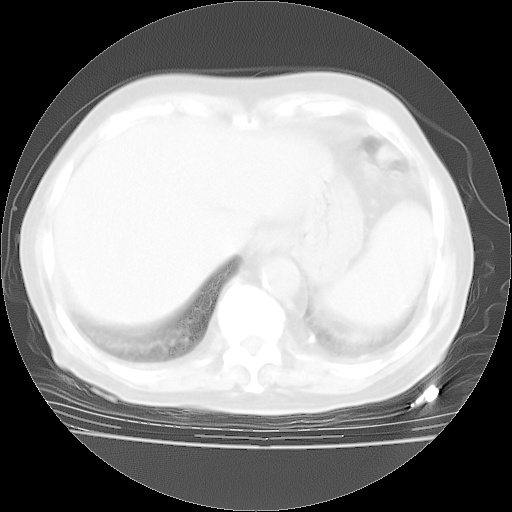

4月28日肺部CT——再次出现类似去年5月9日——透光度降低,“间质性”改变。

4月28日肺部CT——再次出现类似去年5月9日——磨玻璃样、间有“粟粒样”改变。

4月28日肺部CT